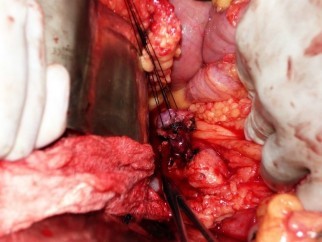

Con la finalidad de extirpar la lesión, se aplicó la técnica de sacabocado, luego se procedió a colocar suturas de seda (Figura 3), a manera de anclaje en las lesiones, y se extirpó la lesión nodular con electrocauterio monopolar (Figura 4). El resultado fue una hemostasia prolija (Figura 5). Finalmente, se procedió a cerrar la transcavidad de los epiplones y la cavidad se cerró en un plano sin colocación de drenajes.

Figura 3 Colocación de suturas de seda para anclaje de la neoplasia

Figura 4 Extirpación del insulinoma en sacabocado con electrocauterio monopolar en modo spray